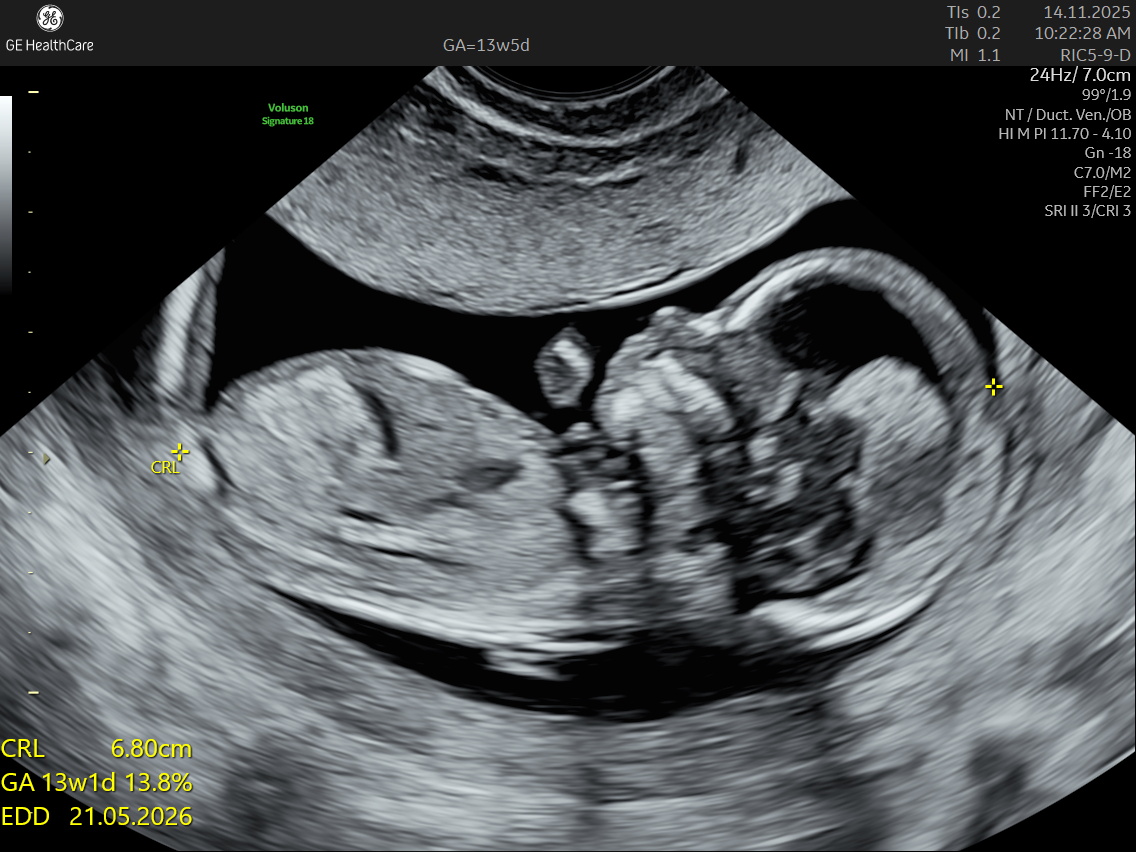

Nuchal Translucency Scan at NESA Institute of Fetal Medicine, Kolkata

NESA Institute of Fetal Medicine offers specialized first-trimester screening for expectant parents, delivering high-precision NT scans between 12 to 13 weeks of pregnancy. Our experienced fetal medicine team ensures accurate risk assessment for chromosomal abnormalities, including Down syndrome, Edwards syndrome, and Patau syndrome.

The NT scan is a non-invasive ultrasound examination conducted in the first trimester (12–13 weeks). It measures the nuchal translucency (the fluid at the back of the fetus’s neck) and combines it with the maternal blood test for a detailed risk profile. NT Scan is an important early screening test for Down syndrome (Trisomy 21), Edwards syndrome (Trisomy 18), and Patau syndrome (Trisomy 13).

How accurate is the nuchal translucency test?